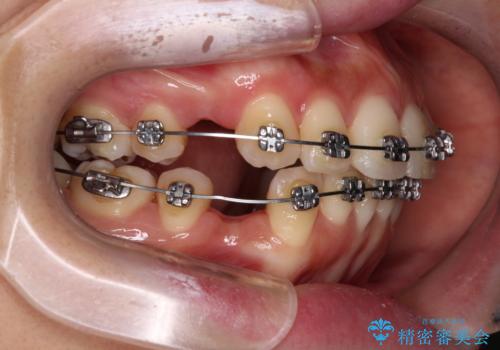

- メタルブラケット

上下ともに歯列が前方に突出していたため、上下左右の第一小臼歯4本を抜去し、ワイヤー装置による矯正治療を行うこととしました。

舌の突出癖がなかなか改善されず、上下前歯の接触がやや甘い状態での仕上がりとなりました。

接触が甘い場合、上顎前歯の叢生が後戻りを起こしやすくなるため、治療終了後の保定期間でも舌のトレーニングを継続するように指示しています。